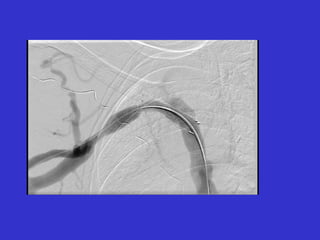

Post-PTA 10 minutes 15 minutes

Elastic Recoil of Central Veins

Immediately Post-PTA 20 minutes Post-PTA stent positioning Return oforiginal stenosis due to elastic recoil phenomenon.